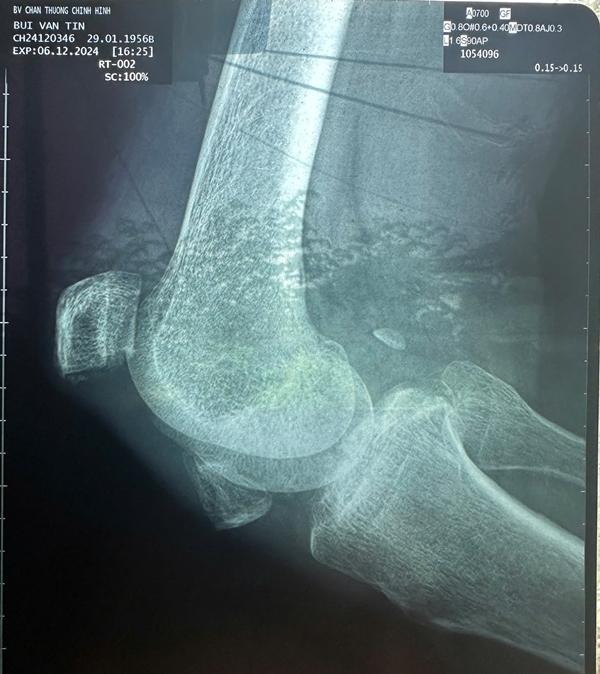

Nhạc sĩ Tô Hiếu mới chia sẻ với Gia đình & Xã hội, Thương Tín sau khi khám tại bệnh viện chấn thương chỉnh hình TP.HCM phát hiện chân phải bị bể đôi bánh chè khớp gối. Bác sĩ nói không thể hồi phục lại được.

Còn chân trái của Thương Tín bị viêm khớp gối nặng, cần uống thuốc điều trị lâu dài. Ngoài ra, bác sĩ lưu ý rằng sức khỏe của nam diễn viên "Biệt động Sài Gòn" hiện rất yếu, chưa thể mổ lấy 2 bánh chè, cần hạn chế đi lại, phải ngồi xe lăn.

Phim chụp của Thương Tín.